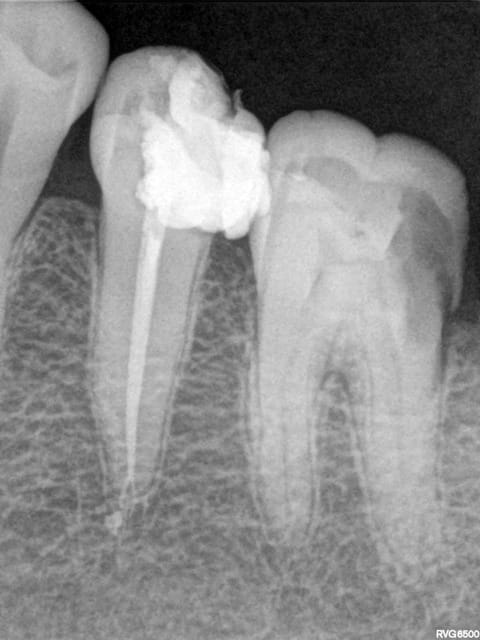

Voila un exemple , ok ,mes endos sont beaucoup moins belles que les tiennes mais elles sont acceptables (gutta-condensator de Densply), je ne pense pas que beaucoup de confrères reprendraient ce travail.

Pour la digue , j'utilise les mini-digues (Meba )qui malheureusement ne permettent pas les rx ( mais il y a le z-root)

Rx 35 vc2t95 - Eugenol